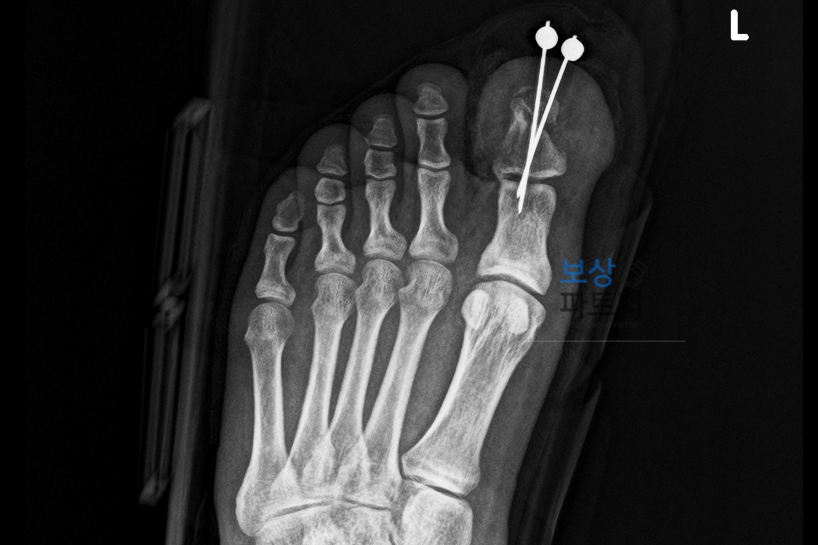

손가락 부상의 아픔이 채 가시기 전, 작업 중 무거운 쇳덩이가 발등 위로 떨어지며 왼쪽 엄지발가락(제1족지) 개방성 분쇄골절이라는 심각한 부상을 입으셨습니다. 이번에도 역시나 골절 부위에 2개의 금속핀으로 고정하는 수술을 받으셔야 했습니다.

저희 보상파트너는 의뢰인의 X-ray, CT, MRI 영상을 전수 정밀 분석하였습니다. 특히 이번 사례처럼 '관절면을 침범한 골절'의 경우, 육안으로는 뼈가 붙은 것처럼 보여도 관절 내부의 미세한 부정유합이나 연부조직의 유착으로 인해 구조적인 운동 제한이 발생할 수밖에 없음을 의학적으로 입증해냈습니다.